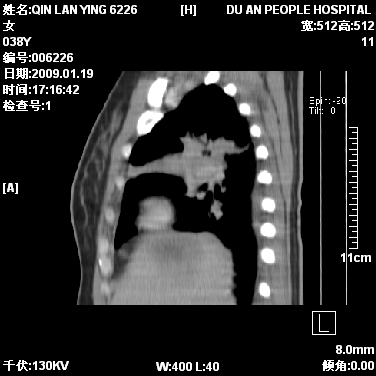

女,38岁,胸疼1个月。wbc:1万4

1)右肺中央型肺癌并右肺上叶阻塞性肺炎、节段性肺不张,纵隔淋巴结转移、右侧胸膜转移、肝脏转移。2)右侧胸腔少量积液。

本病例有几个容易诊断的地方:1、右肺上叶前段支气管闭塞,肺不张。2、淋巴结明显肿大。3、肝脏多个类圆形低密度影呈“牛眼征”改变,高度提示转移。

从影像学角度分析      右肺上叶中央型肺癌,并阻塞性不张、肺炎,纵隔淋巴结、膈顶淋巴结转移。

肝内两个大小不等低密度结节,内可见更低密度影,首先考虑肝内转移瘤,但联想到患者wbc1万4,建议楼主还是做个增强比较明确,除外肝脓肿的可能。